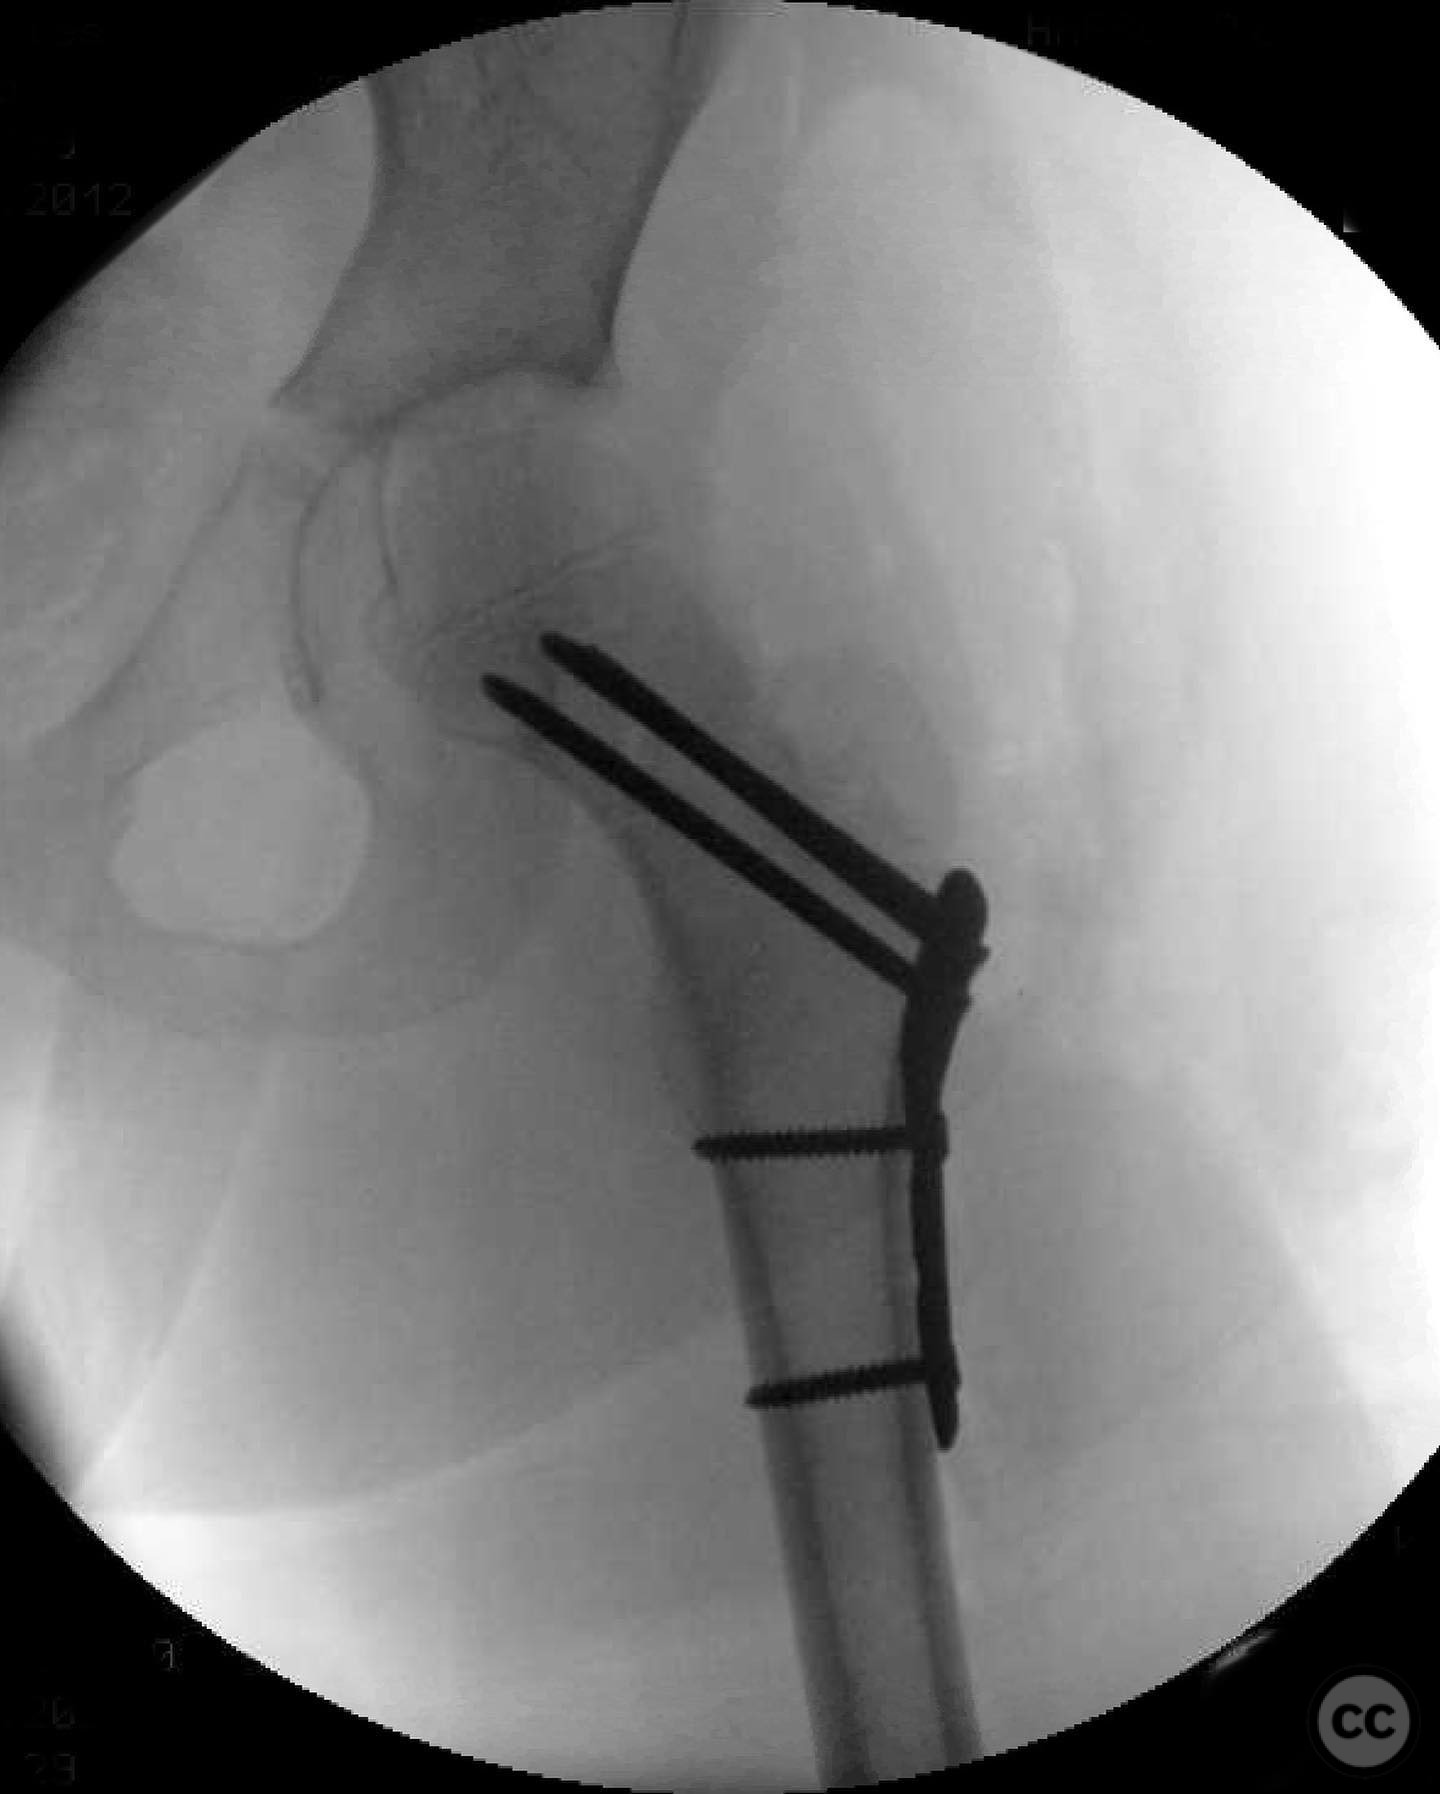

Clinical and radiological findings:  An 8-year-old boy fell approximately 15 feet from a treehouse, sustaining a displaced femoral neck fracture. There were no associated injuries to the head, spine, chest, or abdomen. The initial radiological assessment confirmed a displaced fracture of the femoral neck. Neurovascular examination was unremarkable.

Patient positioning:  Supine position on a radiolucent table to facilitate intraoperative imaging and access to the femoral neck.

Anatomical surgical approach:  A modified Smith-Petersen approach was utilized, involving an incision along the anterior aspect of the hip, allowing for direct visualization of the femoral neck. Subperiosteal dissection was performed to expose the fracture site without compromising the surrounding musculature. A separate lateral approach was employed for the application of fixation devices.

Orthopaedic implants used:   Angle stable static device (specific brand not mentioned).